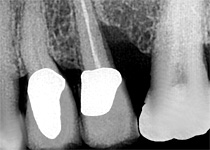

- Parodontitis: Durch tief liegenden, festen Zahnbelag (Subgingivalstein) vertiefen sich die bereits entzündeten Zahnfleischtaschen, das Zahnfach im Alveolarknochen vergrößert sich und die betreffenden Zähne verlieren an Halt.

Schmelz-Matrix-Proteine sind es, die bereits während der Schmelzbildungsphase von Zähnen und bei der Entwicklung des Zahnhalteapparates von Bedeutung sind. Eben solche Proteine werden bei der Behandlung als Gel auf die gesäuberten und vorbehandelten Zahnwurzeloberflächen aufgetragen. In der Folge entsteht ein Eiweißgerüst als Grundlage für die Einspeisung und Anhaftung parodontaler Strukturen des sich erneuernden Zahnhalteapparates.